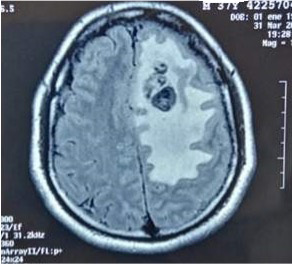

En la tomografía de control se encontraron signos de craniectomía (agujero de trepano) asociada a focos de aire en la región parietal izquierda, edema vasogénico y herniación cerebral parietal izquierda. Por esta razón fue reintervenido quirúrgicamente luego de tres semanas con buena evolución de la lesión (figuras 2 y 3).